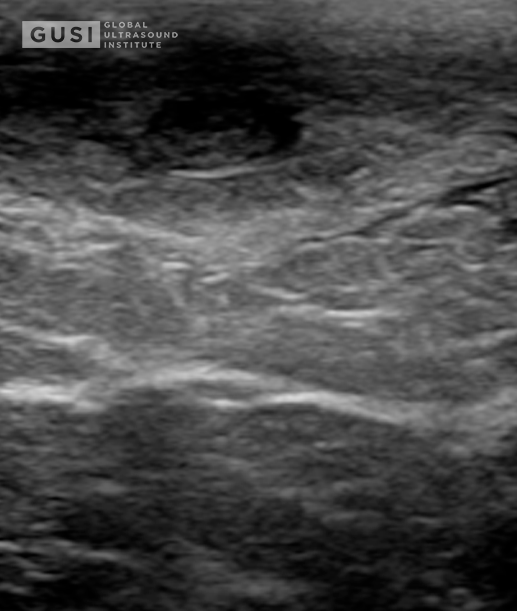

History of Present Illness:

A 28-year-old female with a past medical history of bilateral breast mammoplasty and obesity presents to the Emergency Department with acute onset right breast tenderness, erythema, and edema. She also noted a low-grade fever of 38.5 degrees Celsius accompanying these symptoms. The patient underwent bilateral breast mammoplasty 12 months ago and reported a previous episode, approximately 9 months post-surgery, of a small right breast lesion causing discomfort. This lesion fluctuated in size but resolved without intervention. This time, however, the symptoms were more pronounced, with prominent tenderness, warmth, and redness. There were no overlying skin changes, nipple discharge, or recent trauma to correlate.

Physical Examination of Right Breast:

-

Tenderness: Prominent tenderness on palpation around the developing abscess at 2 o’clock with associated palpable fluctuance.

-

Erythema and Edema: Observable redness and swelling on the outer quadrant mentioned above.

-

Calor (Warmth): Increased warmth over the affected breast area.

-

Rubor (Redness): Noticeable redness around the involved area.

-

No Nipple Discharge: No spontaneous nipple discharge.

-

No Overlying Skin Changes: Absence of skin changes over the right breast.

Management:

An ultrasound-guided needle aspiration successfully drained 20 mL of sanguinopurulent material, which was sent for culture. The patient experienced immediate relief and was discharged home with a prescription for a 10-day course of oral amoxicillin-clavulanate (875-125 mg). She received a recommendation for close follow-up with her plastic surgeon for further interventions.

Microbiological Findings:

The initial Gram stain revealed Gram-positive rods, and 5 days later, laboratory data yielded pansensitive growth of Cutibacterium (Propionibacterium) avidum. The patient completed the antibiotic course and scheduled ambulatorial surgical intervention of an epidermoid cyst.